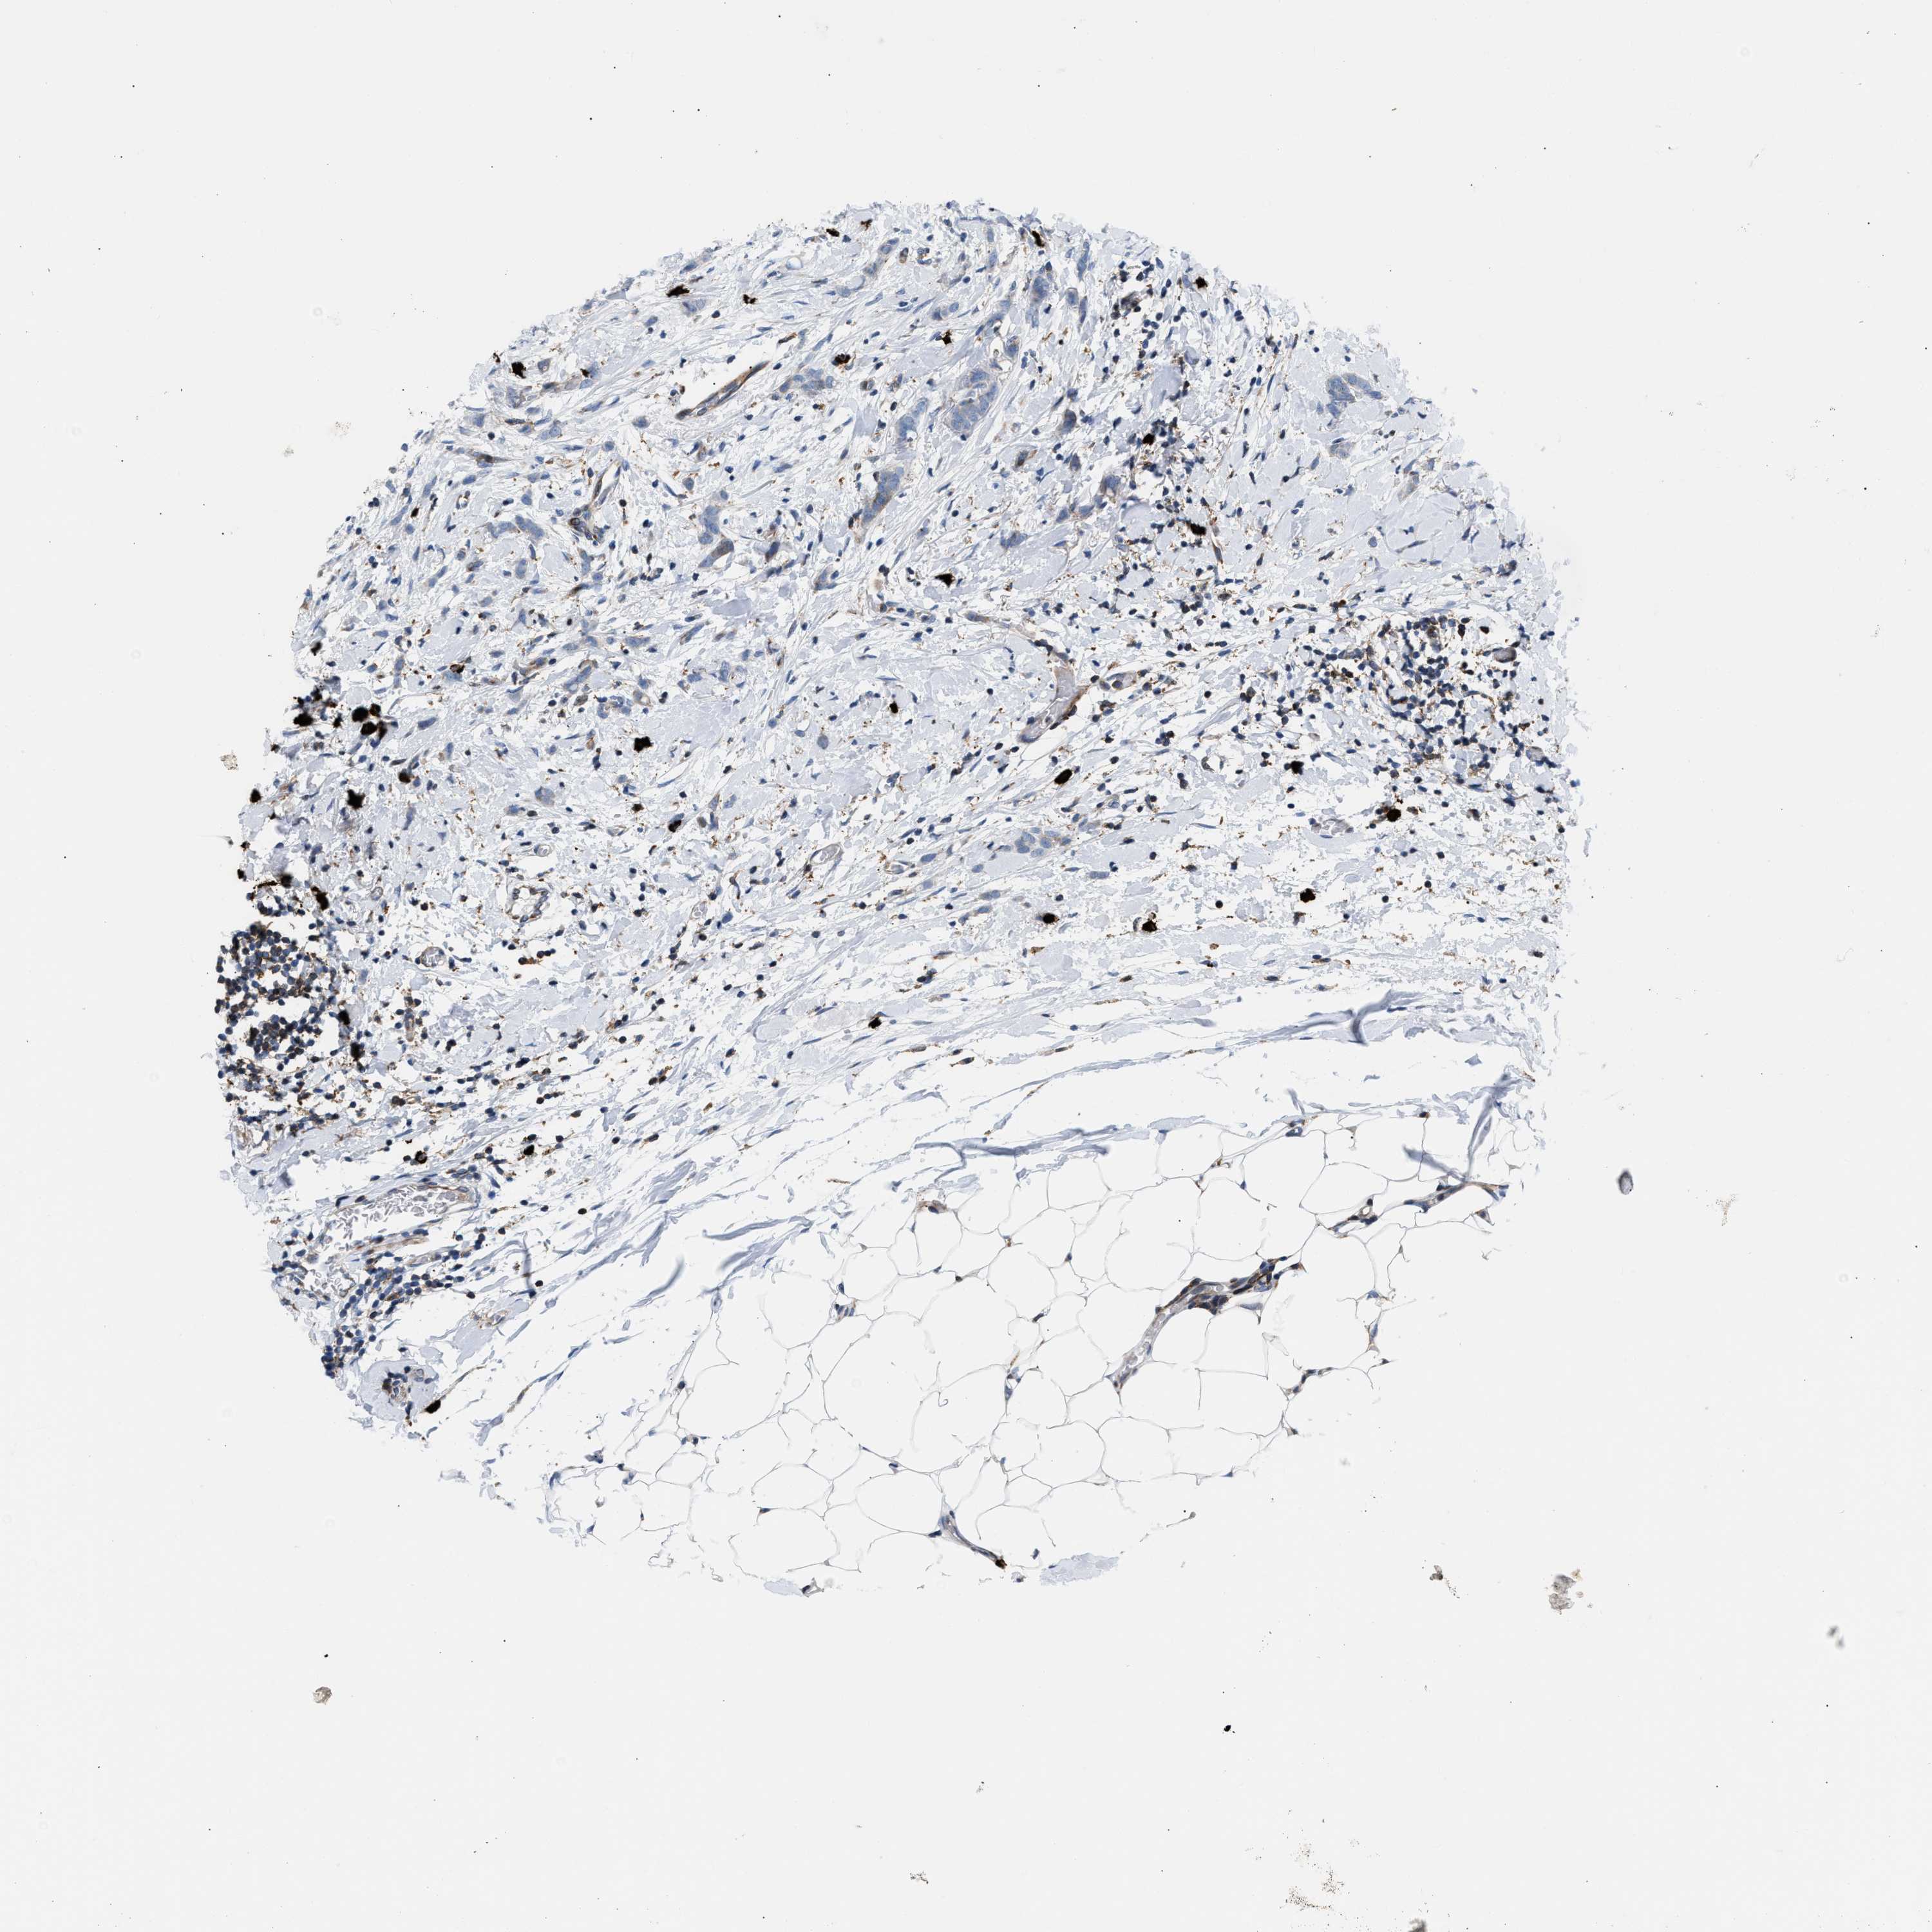

BRCA TCGA BRCA VALIDATION PROTEIN EXPRESSION